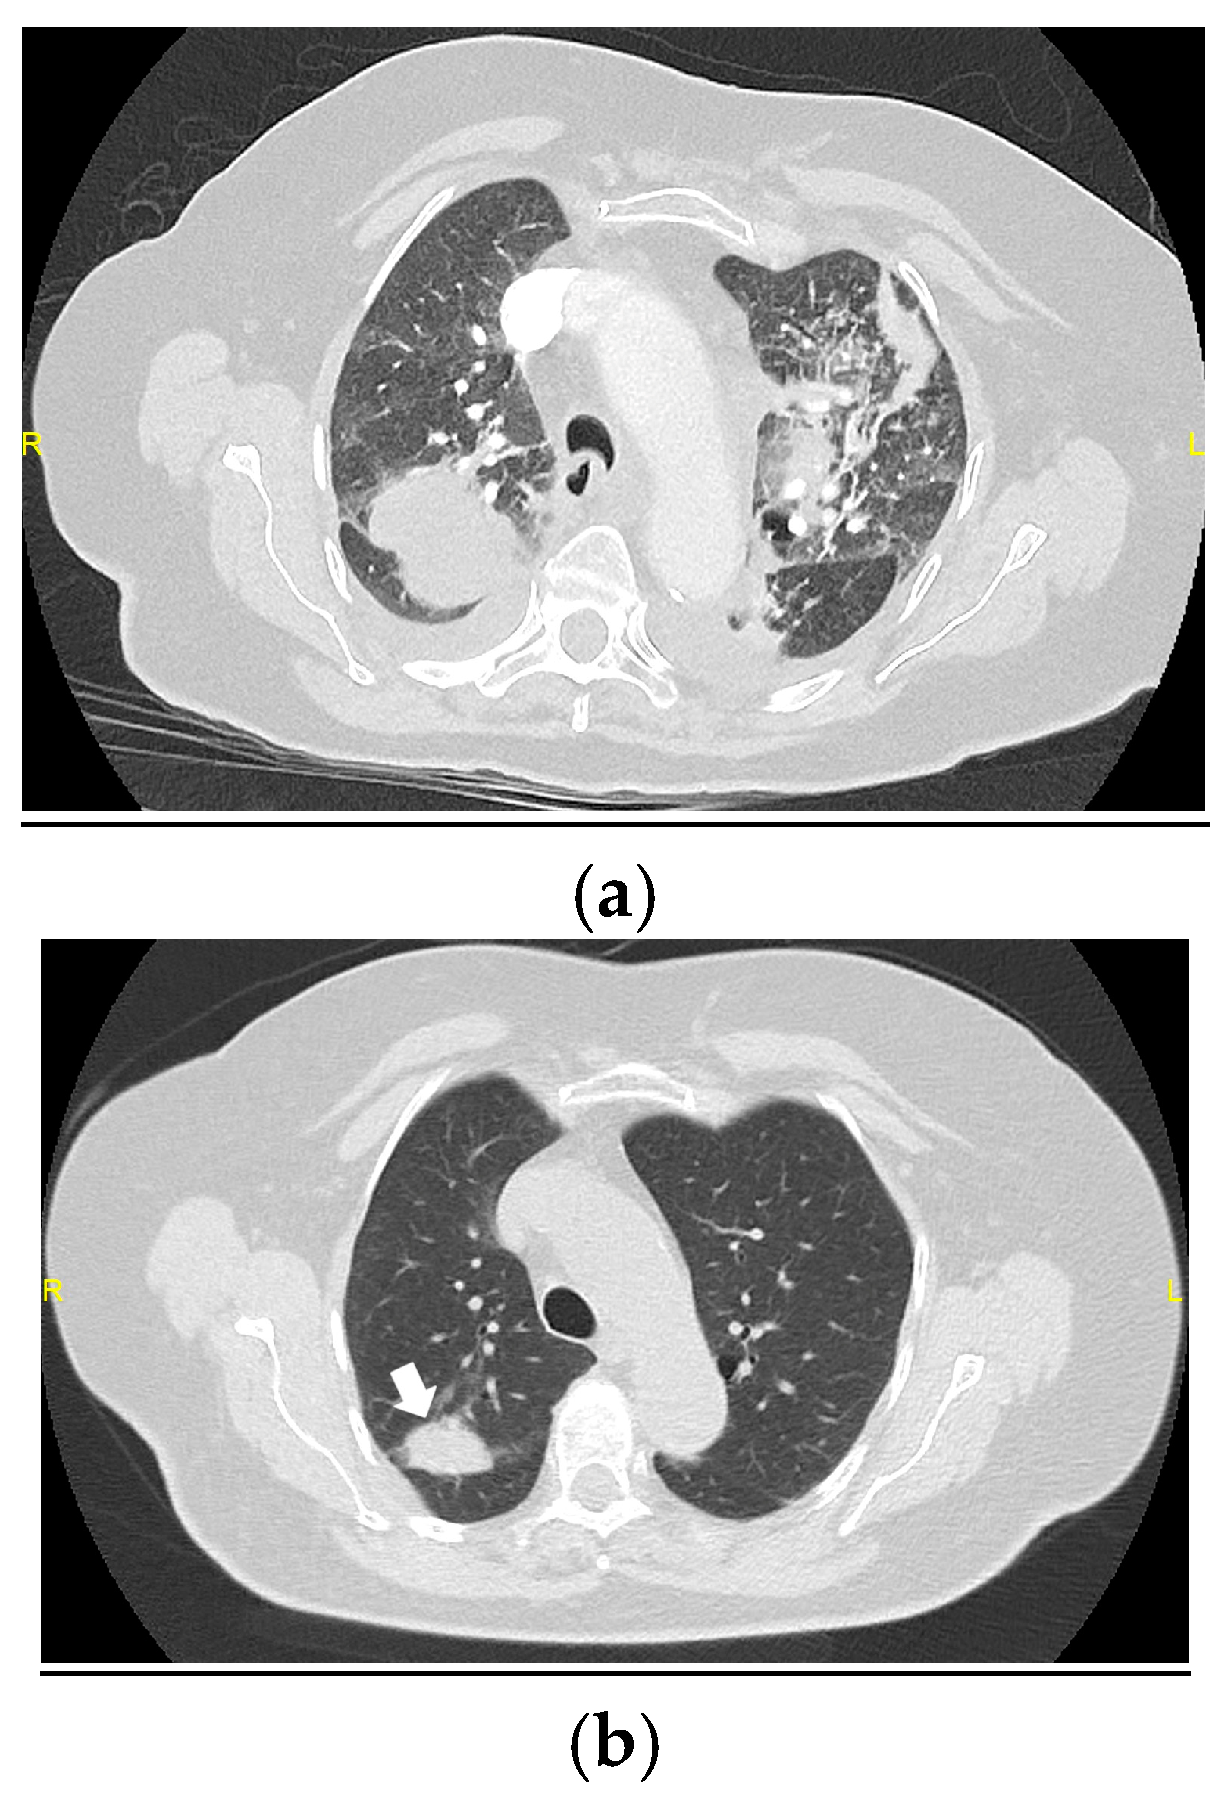

3.2. Changes in the Main Radiological Patterns and Findings from 6 to 12 Months After Hospital Discharge

3.2.1. Radiological Patterns

3.2.2. Main Radiological Findings